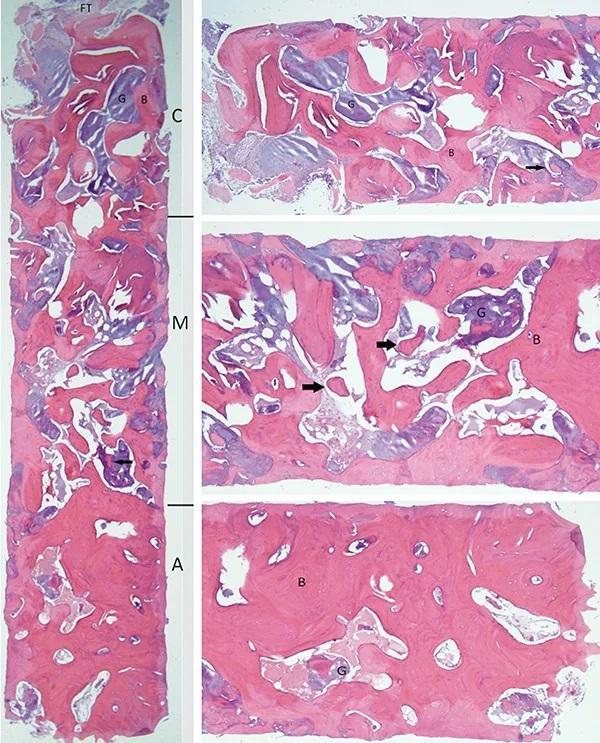

Микроскопическое исследование полученного костного блока выявило как плотную, так и пластинчатую кортикальную кость, а также скопления аморфного базофильного материала трансплантата, содержащего очаги новообразованной остеоидной кости. Кроме того, в самой корональной части образца была обнаружена шапочка из волокнистой соединительной ткани. Блок был разделен на три части по длине: коронковая треть показала наибольшее соотношение остаточного материала трансплантата, и, хотя в остаточном материале трансплантата были выявлены области дистрофических кальцинатов, образования остеоидов не наблюдалось; в средней трети соотношение материала трансплантата к кости составляло примерно 50:50, и были выявлены очаги образования новой остеоидной кости; наконец, апикальная треть показала самую высокую концентрацию пластинчатой кости и наименьшее количество остаточного материала трансплантата (фото 15).

Фото 15. Показан гистологический срез материала костного блока гематоксилином и эозином (H&E). Костный блок был разделен на три трети: C) корональная, (M) средняя, (A) апикальная. В самой корональной части наблюдался колпачок из фиброзной ткани (FT). Фиолетовые области указывают на остаточный материал трансплантата (G), в то время как розовые области указывают на образование пластинчатой кости (B). Стрелка на (C) указывает на очаговую дистрофическую кальцификацию, а стрелки на (M) указывают на очаги образования новой кости. Стрелка на левом изображении (в [M] третьем) также указывает на очаг образования новой кости. (Изображение предоставлено Скоттом Питерсом, доктором медицинских наук, работающим на кафедре патологии полости рта и челюстно-лицевой области Колледже стоматологической медицины Колумбийского университета, Нью-Йорк)